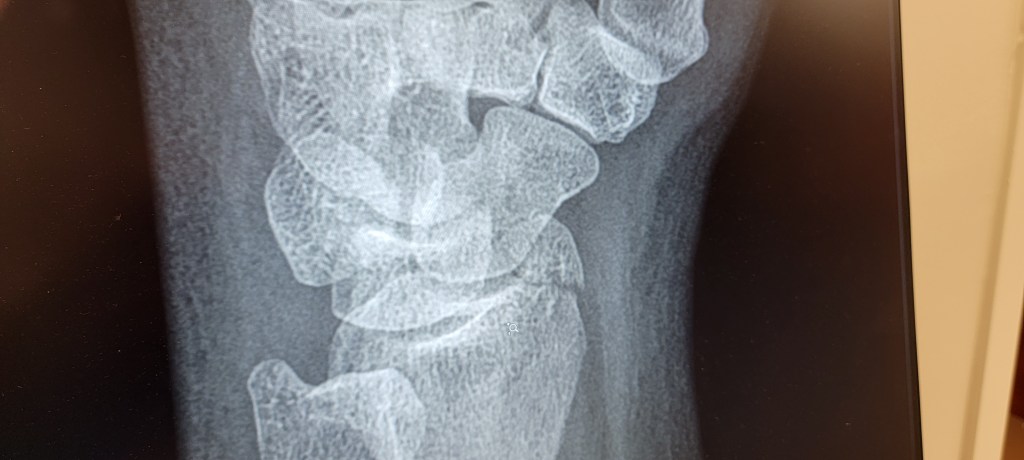

By the time Owen got back from his business trip on Friday, it was obvious that my arm wasn’t going to fix itself. A Walgreen’s wrist brace kept it from wiggling around all willy nilly, but I had to get it looked at. So on a beautiful Saturday morning that would have been a perfect beach day or park day or just-about-anything-else day, we checked our insurance and went to an urgent care. The first one we ubered to had a 3-hour wait and no Xray technician on site. We ubered to a second location in Cape Coral with just a 2-hour wait. After about 1.75 hours, I was taken back and examined. An Xray confirmed that I had a distal radius fracture. Sigh. They gave me a new brace that immobilized my thumb, which, I’ve learned, is an under-appreciated appendage and pretty much rendered my hair undoable for the foreseeable future. I have a name of an orthopedic surgeon and will make an appointment asap. There was a Publix across the street, so we used the opportunity to grab groceries before grabbing an uber back to the boat.

The urgent care doctor said I will probably need to see the orthopedic surgeon two or three times in the next 6-8 weeks, so our Bahamas plans are in limbo. Also, we can’t stay in this marina for much longer, as they have other reservations coming in. We think we might go back to Bimini Basin, but my not being able to pull up the anchor one-handed is going to require some changes in the way we handle things for the near future. We’ll see.

(Update: Saw the surgeon. The bone had already moved right back into place. No surgery required. Hallelujah!)